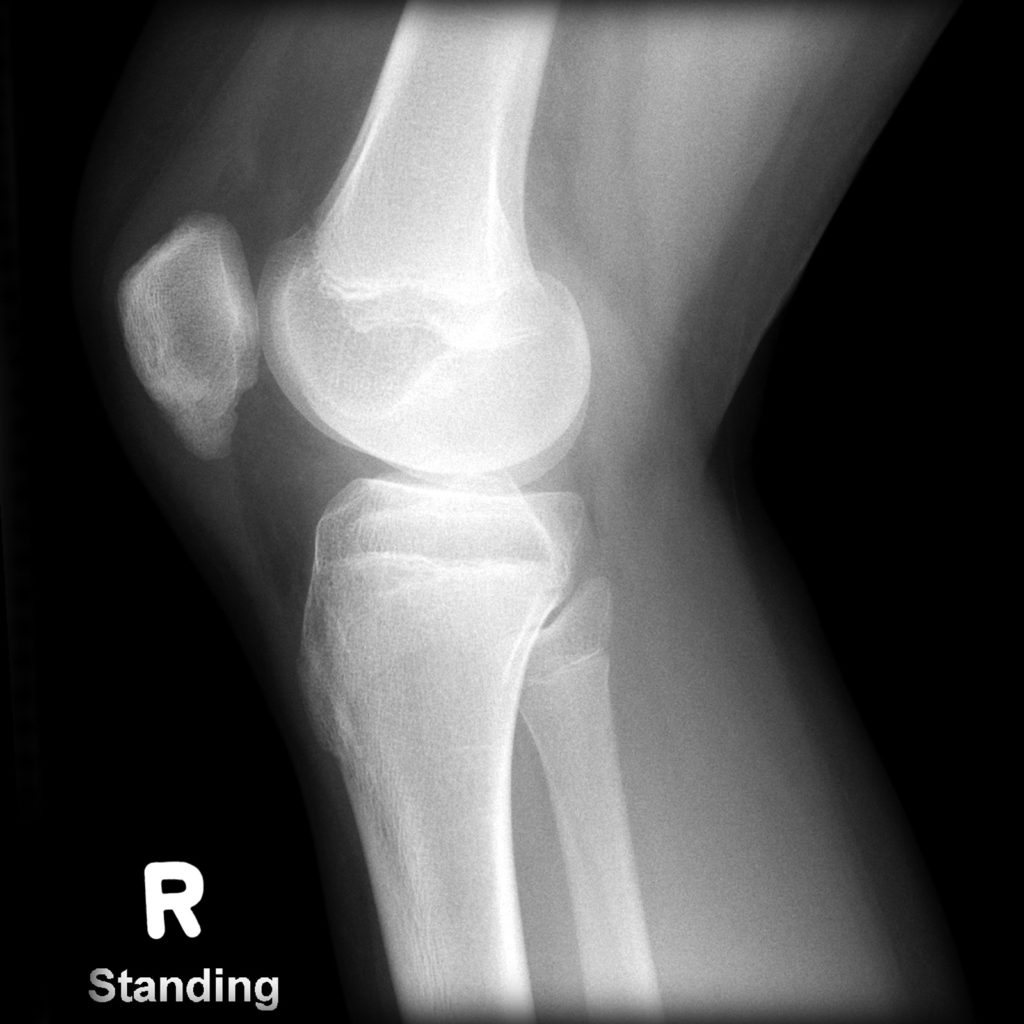

Lateral Xrays of the knee; A preoperative and; B postoperative Jumper's Knee Vs Sinding Larsen In fact, if you have similar. Both conditions are treated the same, but can be differentiated by the location of the pain: Jumper's knee or patellar tendinosis is a chronic insertional injury of the posterior and proximal fibers of the patellar tendon at the site of its origin at the inferior pole of the patella. Jumper's Knee Vs Sinding Larsen.